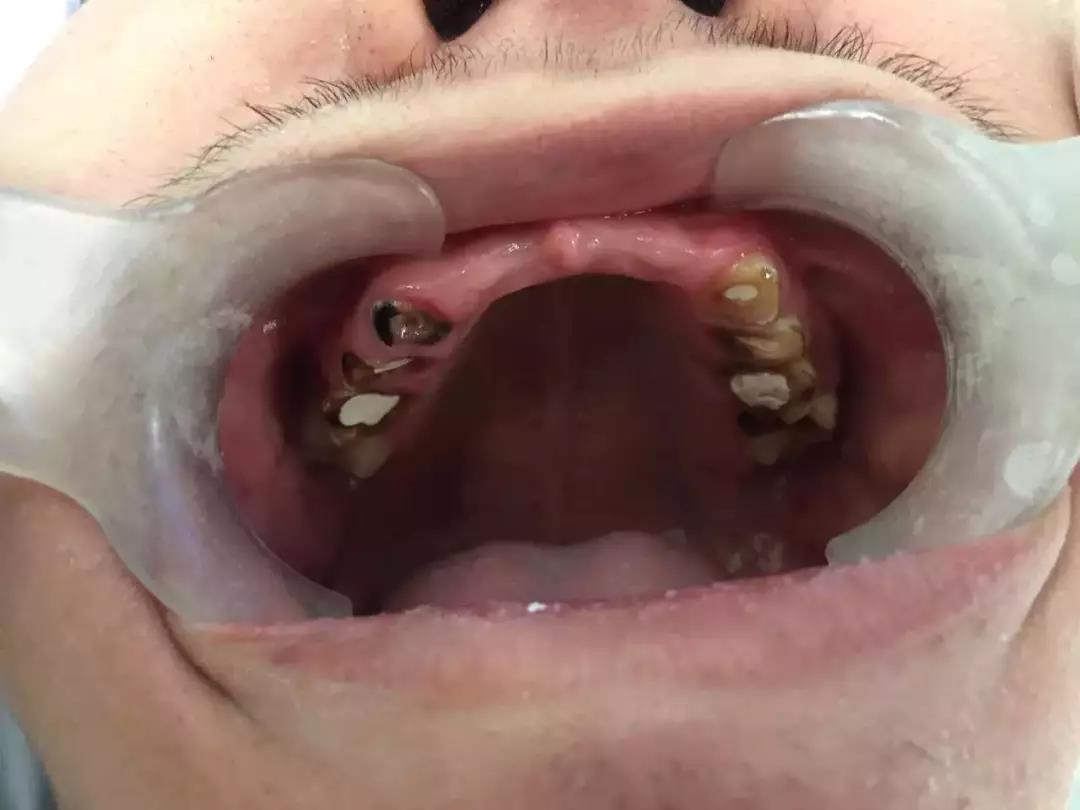

男孩被妈妈带到章主任这里的时候,满口牙齿已经惨不忍睹。

成年人的口腔里,有功能的应该有28颗牙齿,上下12颗门牙+8颗前磨牙+8颗磨牙。

男孩的这28颗牙齿,其中上门牙6颗、下磨牙2颗,因为烂得太彻底,已不得不拔掉了。

还有8颗牙齿因为被饮料腐蚀得脆弱不堪而折断,甚至齐根折断与牙龈齐平了。

满口牙齿中,还算“有点样子”的只剩6颗下门牙,但也被腐蚀得很单薄,牙体几乎变透明了,基本上只要一咬骨头,也会马上碎裂。

因为从小烂牙齿,不能咬硬东西,什么骨头呀、豆子呀、都不能吃,这也影响到了面部骨骼发育,男孩的上颌骨骨量不足,显得窄小,闭着嘴的时候,是“地包天”。他平时不敢笑,要笑的时候,也只好抿着嘴,怕被同学笑话。